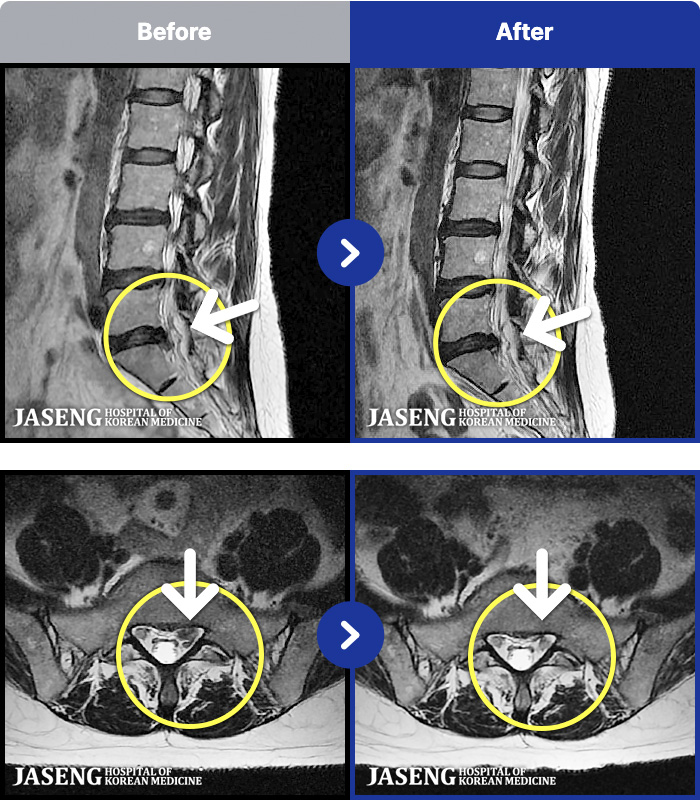

54 MRI ũ ʸ Ȯϼ.

[뱸] 19.11.28~25.05.06